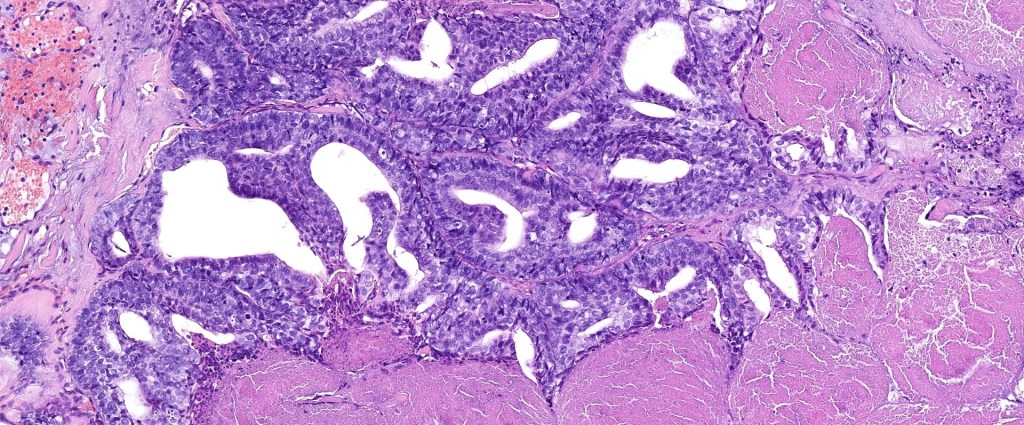

•Papillary component (may include pseuopapillae & true papillae with a fibrovascular core)

•Back-to-back glands with double-layered epithelium

•Cuboidal/columnar with eosinophilic cytoplasm & vesicular nuclei

•Variable pleomorphism & mitotic activity (can appear deceptively bland)

•Variable necrosis & lymphovascular invasion